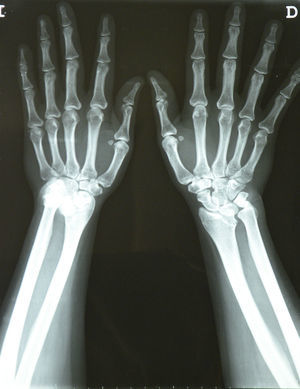

En el estudio radiográfico de muñecas en proyección PA (fig. 2), se evidenció en el carpo derecho los hallazgos típicos de la deformidad de Madelung1: acortamiento del radio en relación con el cúbito, radio curvado con convexidad dorsal y radial, angulación similar de la superficie articular radial distal, incongruencia de la articulación radiocubital distal y subluxación del carpo. En la proyección lateral (fig. 3), se apreciaba arqueamiento anterior del radio y subluxación dorsal de la cabeza cubital; el carpo también se encontraba subluxado cubital y palmarmente en la articulación radiocubital distal, de modo que los huesos del carpo parecían seguir al arqueamiento del radio2. Con el diagnóstico de síndrome del túnel carpiano bilateral secundario a deformidad de Madelung, se planteó derivación a Traumatología para cirugía. Debido a la demora de más de 2 meses, se propuso tratamiento médico con infiltraciones locales de corticosteroides. Se infiltró 1ml de triamcinolona en el carpo derecho, según técnica estándar3. El dolor comenzó a remitir a partir de los 2 días siguientes a la infiltración (EVA: 50/100), desapareciendo completamente el dolor en la revisión a la semana (EVA: 0/100).